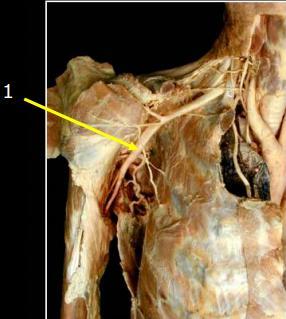

Axillary artery